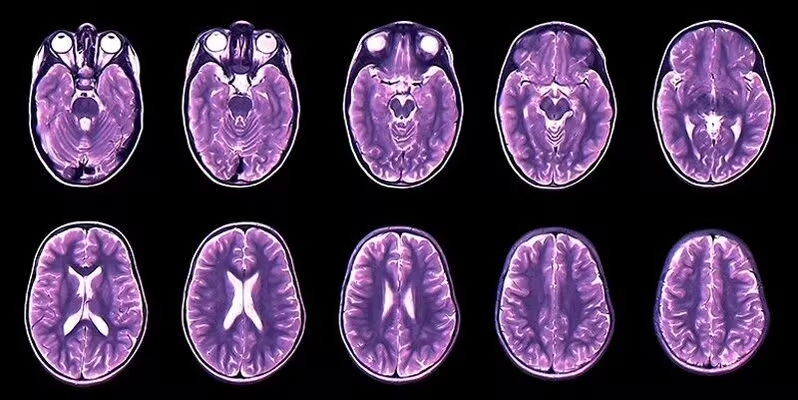

1. Brain Tumor(MRI)Detection 脑肿瘤影像数据集

Brain Tumor(MRI)Detection 是一个用于检测是否有脑肿瘤的医学影像分类数据集,旨在为机器学习模型提供用于脑肿瘤检测任务的 MRI 图像样本。该数据集由磁共振成像(MRI)图像构成,图像被划分为含有脑肿瘤的病例和不含脑肿瘤的正常病例两类。

数据集示例